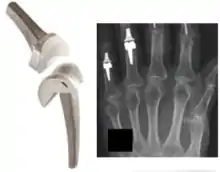

Replacement arthroplasty (from Greek arthron, joint, limb, articulate, + plassein, to form, mould, forge, feign, make an image of), or joint replacement surgery, is a procedure of orthopedic surgery in which an arthritic or dysfunctional joint surface is replaced with an orthopedic prosthesis. Joint replacement is considered as a treatment when severe joint pain or dysfunction is not alleviated by less-invasive therapies. It is a form of arthroplasty, and is often indicated from various joint diseases, including osteoarthritis and rheumatoid arthritis.

Two previously popular forms of arthroplasty were: (1) interpositional arthroplasty', with interposition of some other tissue like skin, muscle or tendon to keep inflammatory surfaces apart and (2) excisional arthroplasty in which the joint surface and bone were removed leaving scar tissue to fill in the gap. Other forms of arthroplasty include resection(al) arthroplasty, resurfacing arthroplasty, mold arthroplasty, cup arthroplasty, and silicone replacement arthroplasty. Osteotomy to restore or modify joint congruity is also a form of arthroplasty.